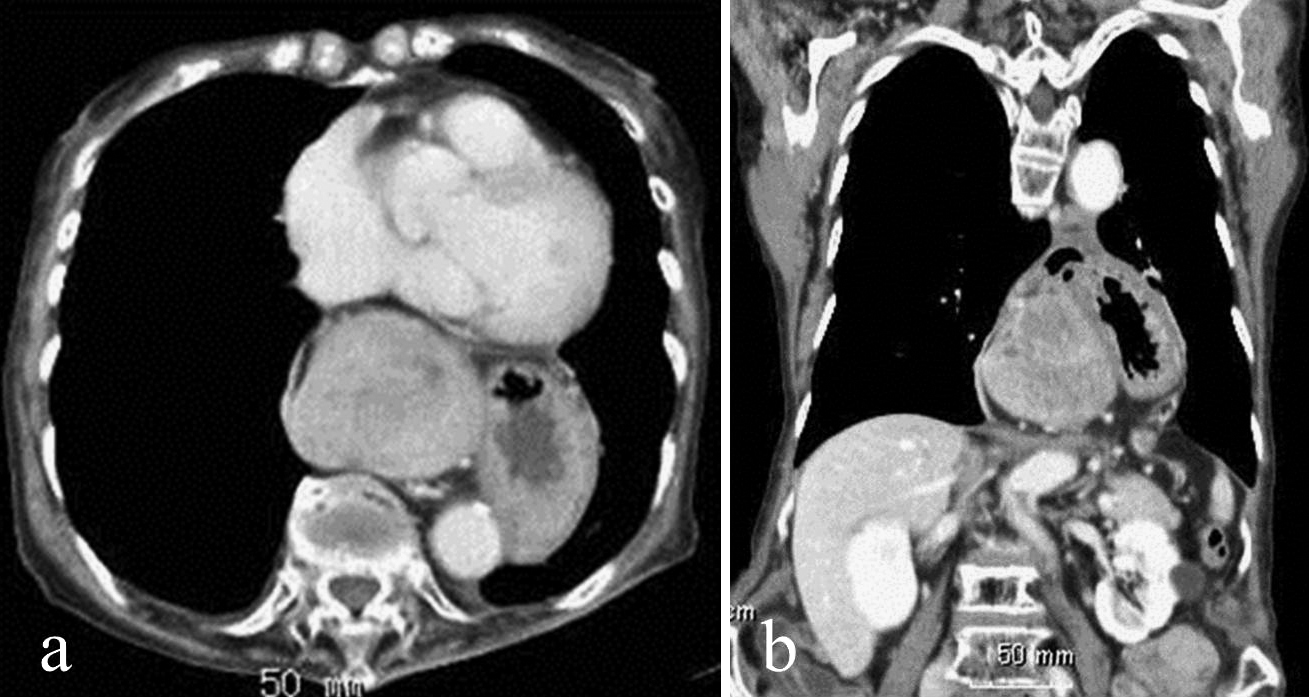

X 線検査は、医療従事者が症状がない場合に食道裂孔ヘルニアがあるかどうかを確認したり、胃食道逆流症 (GERD) 、胸やけ、胸痛などの他の症状がないか検査したりするのにも役立ちます。

X 線、バリウム摂取、CT スキャンは、医療専門家が診断を確認するのに役立ちます。